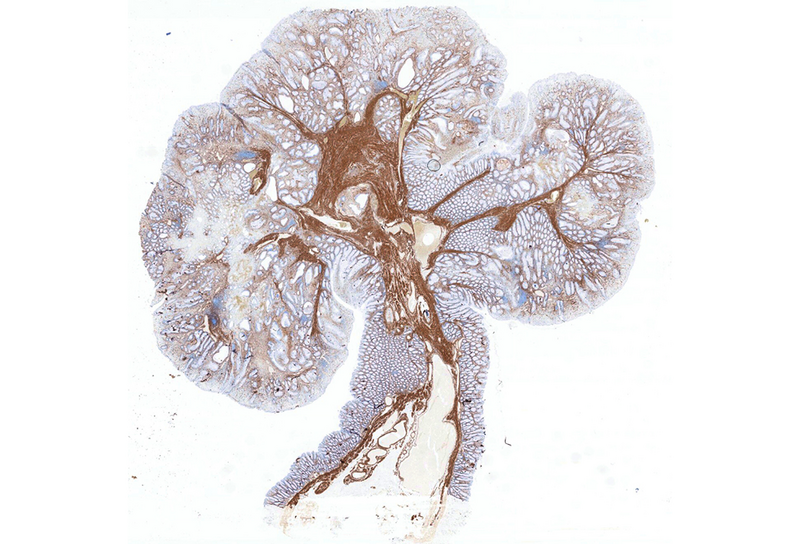

Histologically, the lesion exhibited a complex lobulated architecture (Panel A), with central cores of ramifying bands of smooth muscle extending from the muscularis mucosae into the lamina propria, configuring an arborizing pattern (Panel B). The epithelium exhibited neither cytologic nor architectural atypia and was regarded as reactive (non-dysplastic), with some glands showing dilation and distortion (Panel C). Recovering epithelium was observed on the surface, together with granulation tissue (Panel D).

Notably, the lesion demonstrated beginning pseudo-invasion, defined by the presence of misplaced benign glandular elements extending into the upper part of the stalk. There was mild inflammation of the lamina propria, abundant hemorrhage and hemosiderin-laden macrophages were also observed (Panels E-F). Immunohistochemistry for desmin and smooth muscle actin (SMA) was performed to highlight the smooth muscle fibers (compare Panel B) and emphasize the typical lobulated and arborizing architecture of this type of polyp.